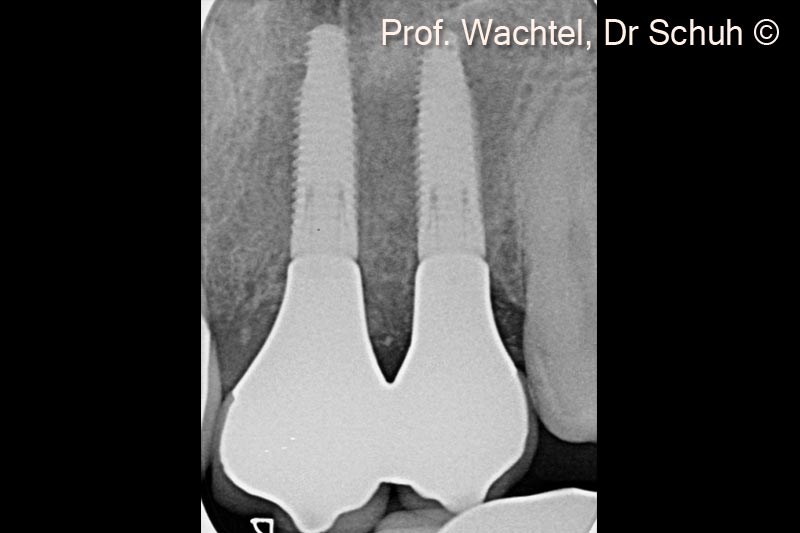

4. X-ray of the 2 implants: #21 and #22. Note the harmonious hard tissue architecture